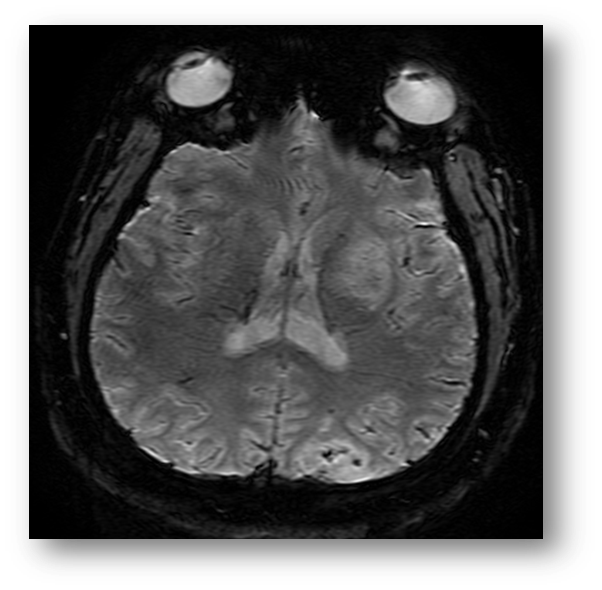

Refer to caption

Figure 6: DWI showing hyperintensity in the left PCA and MCA distributions, consistent with acute ischemic stroke.

The diffusion-weighted MRI (DWI) modality exploits the Brownian motion of water molecules within a sample, and the relative phase shift in moving water versus stationary water. The Apparent Diffusion Coefficient (ADC) is a parameter which can be mapped to provide diagnostic information. In acute ischemic stroke, cytotoxic cellular injury results in axonal edema and a subsequent decrease in Brownian motion. This is manifested as a hyperintensity on DWI and a hypointensity on the corresponding ADC map. Figure (6) is a DWI showing hyperintensity in the left MCA and PCA distributions, consistent with acute ischemic stroke. Figure (4) is an ADC map showing hypointensity in the left MCA distribution, consistent with acute ischemic stroke. Figure (5) shows an ADC map with a left parieto-occipital hypointensity reflecting left posterior circulation acute ischemic stroke. In the subacute setting, the ADC may normalize and even increase due likely to ischemia-associated remodeling and loss of structural integrity. The differential for hyperintensity on DWI includes hemorrhagic stroke, traumatic brain injury, multiple sclerosis, and brain abscesses  [62, 11, 95, 24]. DWI has long been shown in animal models to be more efficacious than T2subscript𝑇2T_{2}-weighted imaging for the early detection of transient cerebral ischemia [73, 77, 28]. Additionally, DWI has been shown to be highly efficacious in the early detection of acute subcortical infarctions [100]. DWI in conjunction with echo-planar imaging has been shown to effectively discriminate between high grade (high cellularity) and low grade (low cellularity) gliomas [104]. Of note, in spite of the relatively high specificity and sensitivity of DWI in the early detection of acute ischemic stroke, there is a small subset of stroke patients who evade DWI detection in spite of clinically evident stroke-like neurological deficits [2]. DWI tractography or diffusion tensor imaging is a form of principal component analysis in which the dominant eigendirection is used to determine the path of an axonal tract in a given voxel. This method has shown potential for further elucidation of neuronal pathways in the brain.